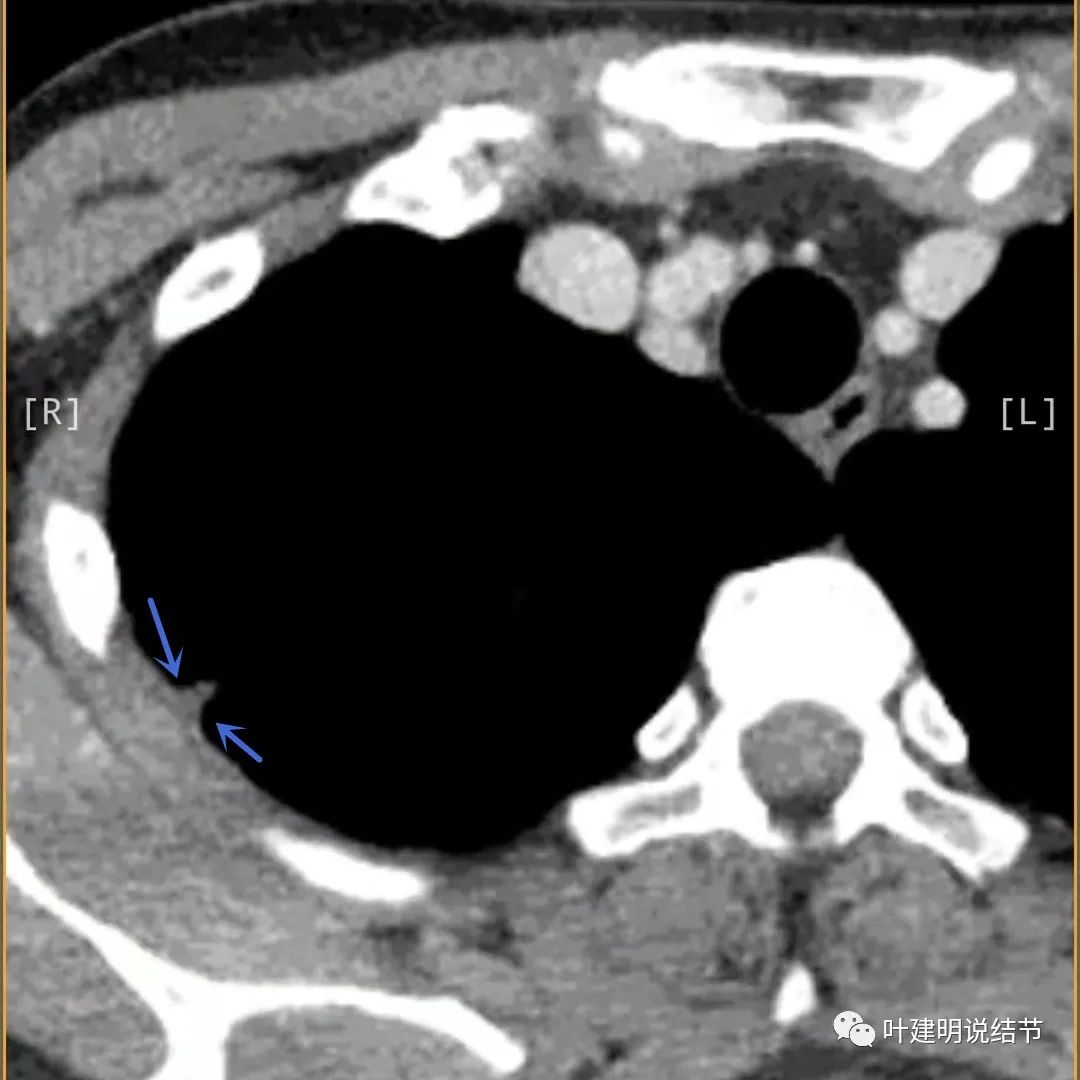

胸壁侧病灶较厚,模糊(蓝色箭头),仍见卫星灶(绿色箭头)

病灶邻近胸膜异常增厚(蓝色箭头)

有卫星灶(绿色箭头),邻近胸膜明显增厚,且模糊,边不清